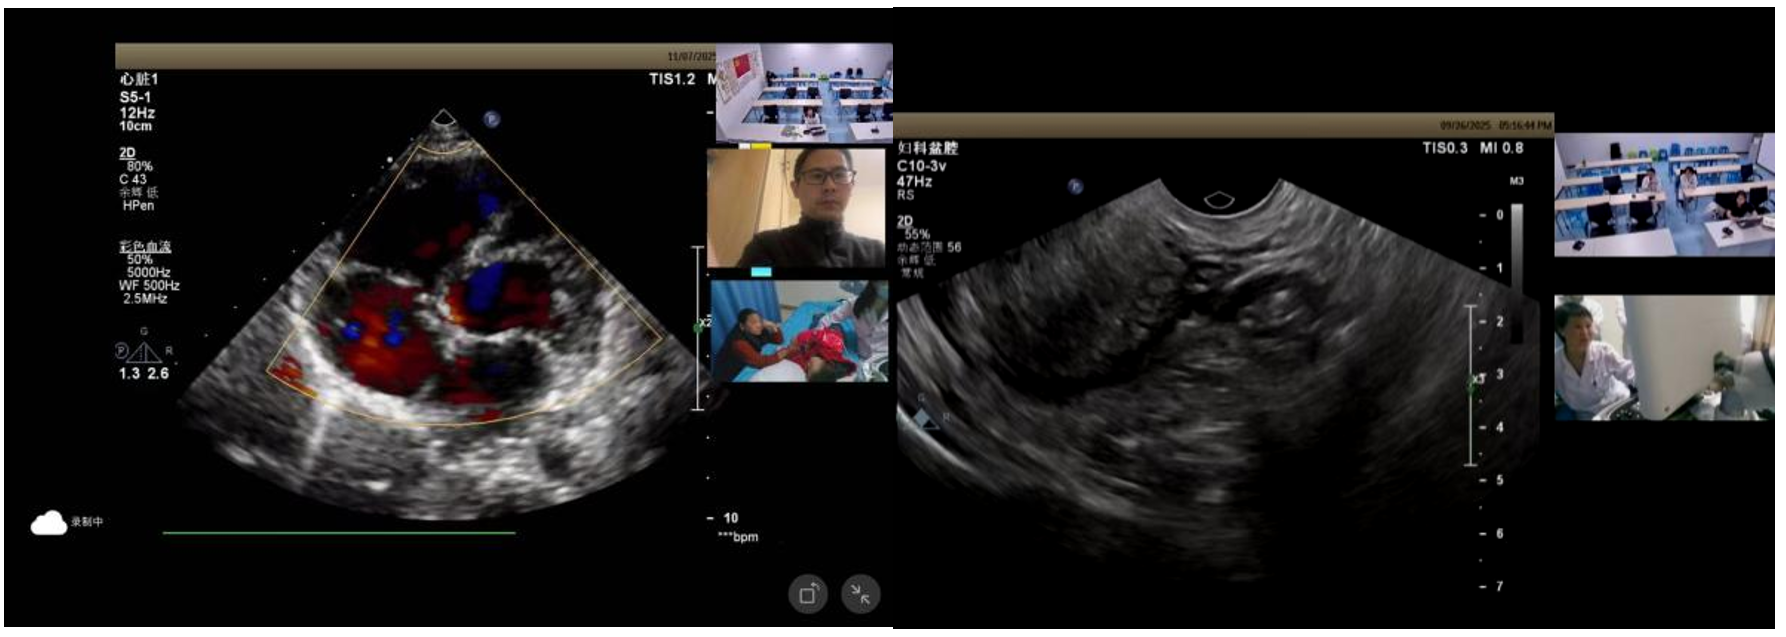

2025年11月,为推动优质超声技术资源下沉基层,服务襄阳地区广大群众,提升区域超声诊断同质化水平,襄阳市远程超声质控中心积极组织开展“智超月鉴·襄阳站”系列活动。该活动由湖北省超声影像诊断与治疗质量控制中心主办,通过远程会诊设备实现了超声图像与视频的实时传输,开展远程实时视频会诊。

本次活动依托“瑞影云++”平台,实现多人、多区域实时在线互动,采取省、市、县三级联动的高效协同机制:

本次远程会诊涵盖心脏、甲状腺、乳腺、妇科、肝脏等多个部位,技术应用全面,包括实时二维超声、彩色多普勒、弹性成像、超声造影等,充分展示了日常诊疗中的主流超声技术手段,切实提升了基层医院对各类疾病的识别与诊断能力。